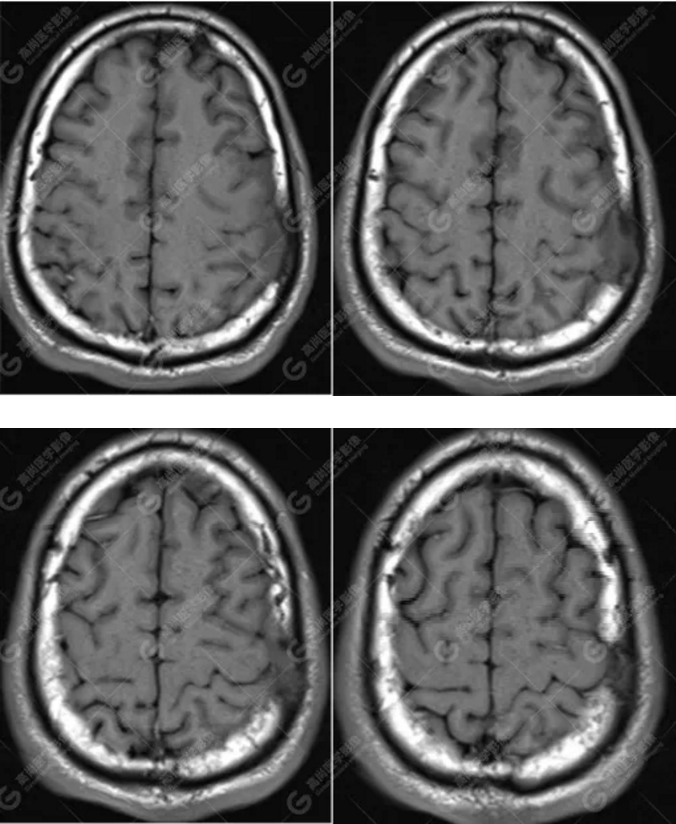

中年男性,反復(fù)出現(xiàn)手腳抽搐、暈倒伴意識(shí)喪失3年余,臨床擬診癲癇發(fā)作,后到高尚醫(yī)學(xué)影像診斷中心行MR檢查。

MR圖像

左側(cè)額頂部顱骨骨質(zhì)破壞并相鄰硬腦膜增厚強(qiáng)化,考慮Rosai Dorfman病(RDD)可能,需與朗格漢斯細(xì)胞組織細(xì)胞增生癥鑒別。

本病多累及淋巴結(jié),原發(fā)于中樞神經(jīng)系統(tǒng)而無(wú)身體其他部位淋巴結(jié)腫大者罕見,低于4%。顱內(nèi)RDD好發(fā)于中年男性,多表現(xiàn)為顱內(nèi)腦實(shí)質(zhì)外的單發(fā)或多發(fā)腫塊,好發(fā)于大腦凸面、鐮旁、鞍區(qū)及海綿竇旁,絕大多數(shù)病例都與硬腦膜密切相關(guān),腫塊多位于硬腦膜外或硬腦膜下。

總之,顱內(nèi)RDD是一種罕見的硬腦膜良性病變,若 MRI發(fā)現(xiàn)顱內(nèi)基于硬腦膜扁平或匍匐生長(zhǎng)的孤立或者多發(fā)腫塊,CT 檢查未見鈣化,而MR檢查T2WI及 DWI呈低信號(hào),增強(qiáng)明顯均勻強(qiáng)化,應(yīng)考慮到 RDD 的可能。